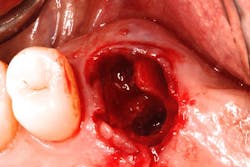

The authors noted a paradigm shift in their practices over the last several years. Hattingh et al. published a technique article regarding immediate placement of ultrawide diameter implants in molar sockets.14 Instead of the more traditional protocol that involved diagnosis of a nonrestorable molar with subsequent extraction, graft, osseous healing, implant placement, osseointegration, and implant restoration, the authors adopted an accelerated treatment protocol due to the availability of site-specific implants.

The original protocol generally required 6–18 months for patients to receive implant-retained restorations. The accelerated treatment protocol typicallySingle-/multiple-unit/full-arch treatment with and without immediate occlusal loading